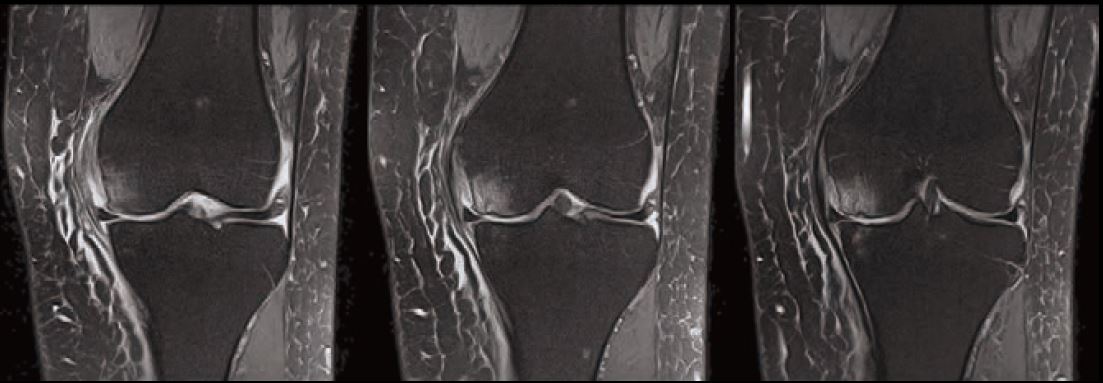

Випадок 1. Велике коліно

Жінка 67 років скаржиться на постійний медіальний біль у коліні.

• Відносно рясний внутрішньосуглобовий випіт.

• Остеоартритне ураження стегново-гомілкового суглоба в медіальній частині зі змінами субхондральної кістки, що може відповідати стресовому перелому.

• Дегенеративна сторона заднього рогу медіального меніска.

Рис. 3 Co FSE PD FS, товщина зрізу 3 мм, роздільна здатність 0,6 мм.